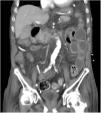

An 81-year-old man with a history of type 2 diabetes mellitus was admitted to our hospital because of abdominal bloating. He had started taking voglibose six days earlier. Physical examination showed abdominal distension, but no abdominal tenderness. Contrast-enhanced abdominal computed tomography revealed an expanded intestinal tract and portal emphysema (Fig. 1). Voglibose was suspended, and the patient underwent emergency laparotomy for suspected non-occlusive mesenteric ischemia. However, there were no signs of intestinal necrosis or perforation (Fig. 2). Bowel decompression was then performed. Computed tomography was carried out on the seventh day of hospitalization, showing no portal emphysema (Fig. 3), and oral diet was started on day 10. The patient’s clinical course was uneventful, and he was transferred to a long-term care hospital on day 24. Portal venous gas has been known to be a rare complication in patients taking alpha-glucosidase inhibitors (α-GIs) and could result from pneumatosis cystoides intestinalis, rather than intestinal ischemia.1,2 It can be managed conservatively, and unnecessary surgical treatment should be avoided.